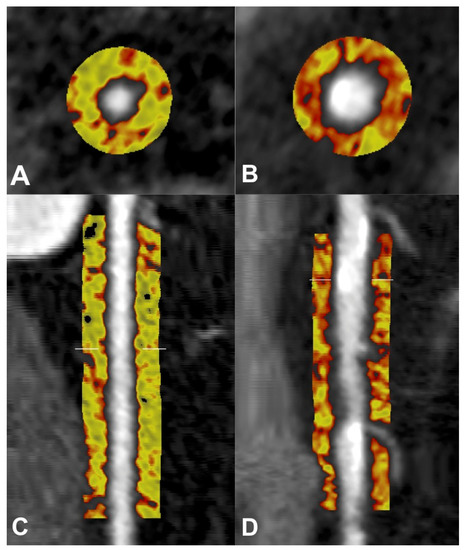

5.2. Pericoronary Fat Attenuation Index